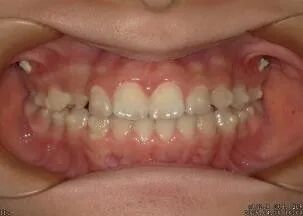

③牙列不齐清洁困难 ④牙齿矫正中和牙齿矫正后

①检查口腔情况 ②拍治疗前口内照片 ③牙菌斑染色

④拍染色后口内照片 ⑤洁牙 ⑥抛光